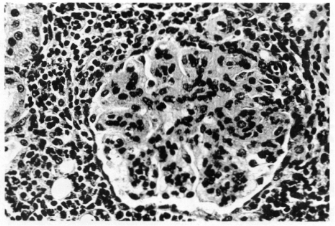

Fig 1—Affected glomerulus Irom a mink with AD. The glomerulus is avascular with large amounts of eosinophilic granular material. Periglomerular infiltration of plasma cells and a few lymphocytes are also evident.